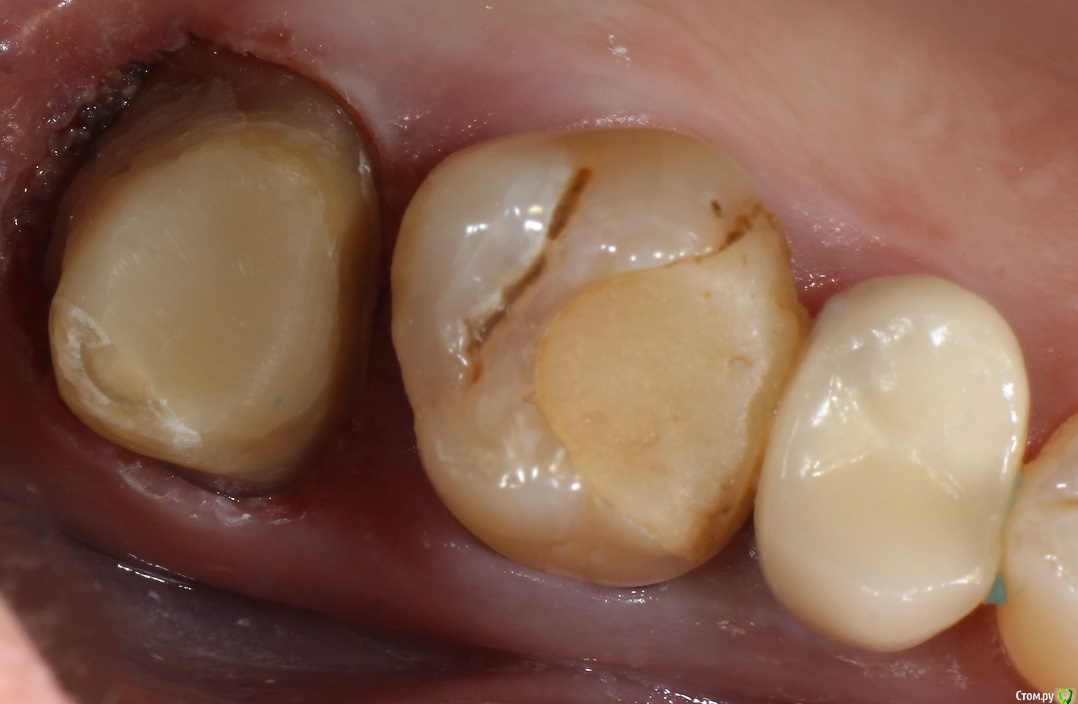

Кейс под названием: Что для тебя успешное эндо?

Пациент: девушка 16 лет. Задача дотянуть зуб сколько сможем по времени, затем имплантация.

Исходная ситуация:  симптоматический апикальный периодонтит. Отломок в медиально-щечном канале.IMG_20210716_134030.thumb.jpg.0b754f1cf44f10a3d2e05ed70884f5b7.jpg

Бился примерно 2 часа, Прошел медиально-язычный. Немного обошел обломок, за ним стопорюсь. Дистальный глухо. Оставил пульпосептин, готовился к удалению.

На следующем приеме жалоб нет, принял решение пломбировать что есть.

IMG_20210716_134113.thumb.jpg.2e302712b90b1c8656830a1d42006bcd.jpg

С пацом решили: если за 3 месяца не появится болей, и в прицельном не появится разряжение - то коронуем.

3 месяца спустя:

IMG_20210716_134129.thumb.jpg.71631666cf042a4c7352572d6c371b77.jpg

Устанавливаем коронку.

Прошло 1.5 года.

Звонит: ходуном ходит зуб. Думаю: ну, здравствуй, обострение, здравствуй, удаление. Пришла, оказывается расцементировка коронки. Делаем снимок:

IMG_20210716_134216.thumb.jpg.209b4330c838774d9bf6e170ae51304f.jpg